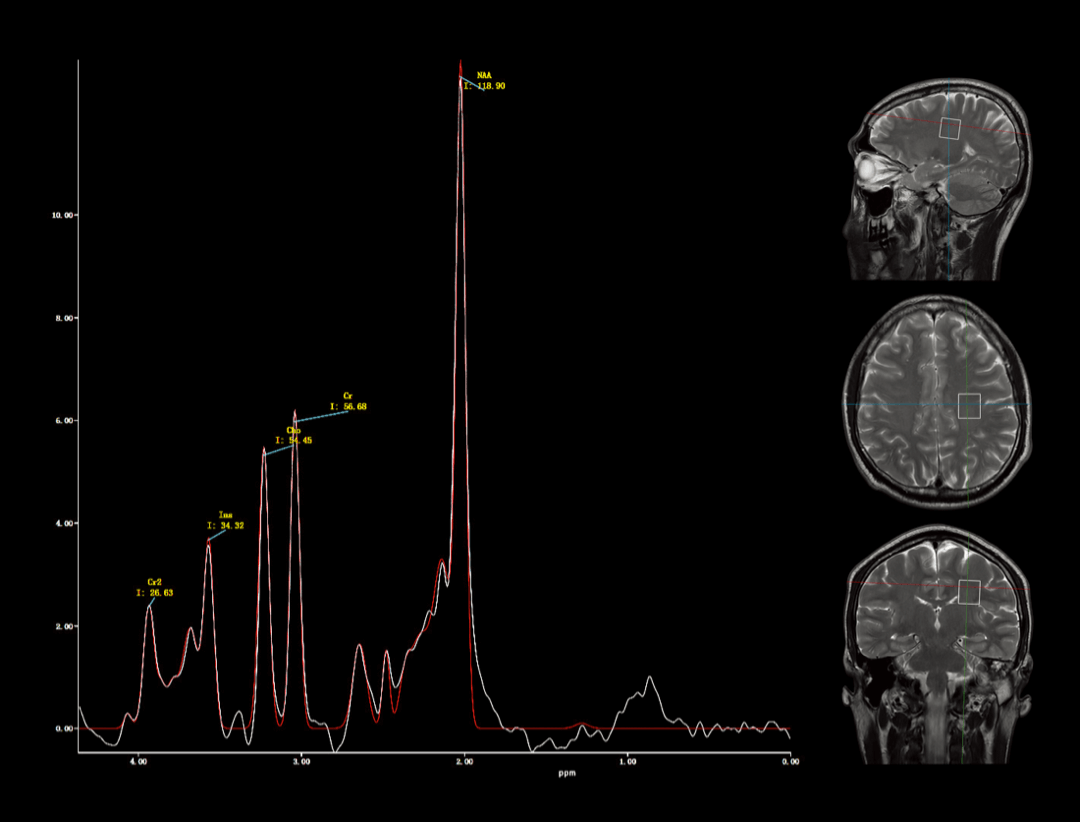

波谱成像

用于研究人体内代谢含量分析,完成活体组织代谢物水平的无创检测。